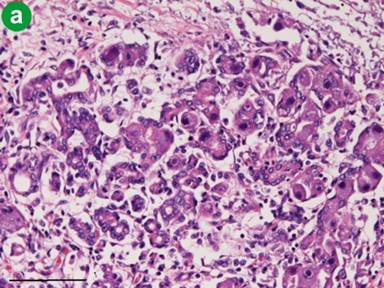

Figure 3. Cytomegalic inclusions. a. The acinar cells and ductal cells contain numerous cytomegalic inclusion bodies (Bar=100µm; H&E, x200). b. The cells with cytomegalic inclusions are positive for immunoreactive cytomegalovirus (Bar=100µm; immunostaining, x200). |

An autopsy revealed severe necrotizing acute pancreatitis (Figure 1). The lungs showed interstitial pneumonia. An aortic aneurysm was present. Histologically, the pancreas showed broad necrosis and the infiltration of neutrophils and lymphocytes (Figure 2). Severe fat necrosis was also recognized. Numerous large inclusions of CMV were found in the acinar and ductal cells of the pancreas (Figure 3). Degenerated and necrotic acinar cells also contained numerous CMV inclusions (Figure 4). The islets of Langerhans were free of CMV inclusions.